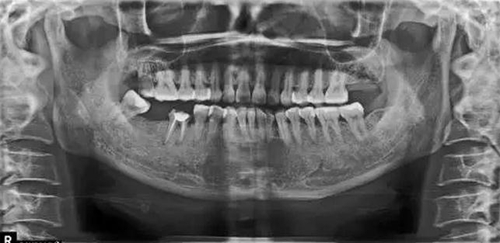

X片上可見T女士左上后牙缺失。根據(jù)患者口內(nèi)和全身狀況。制定計劃為:右上后牙種植修復(fù)。